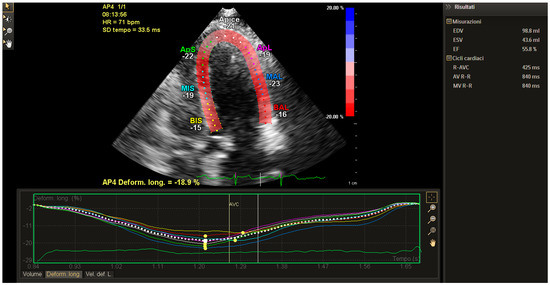

2. Technical Considerations for Strain Analysis

3. Clinical Applications of Strain for the Early Clinical Detection of Myocardial Damage

4. Strain in Cardio-Oncology